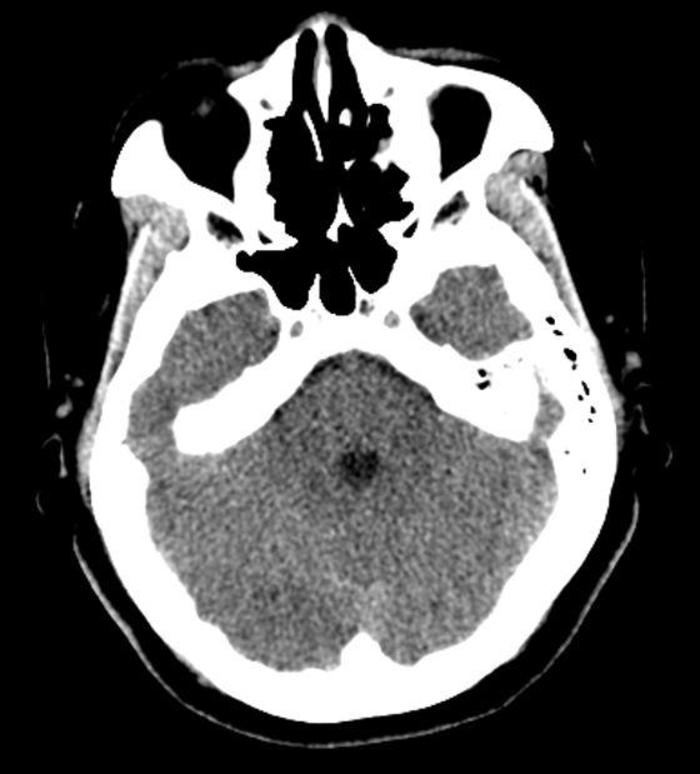

由于体内有金属植入物,不能做磁共振,所以做CT检查,排除肿瘤。不过CT是看不到血管压迫神经情况的。